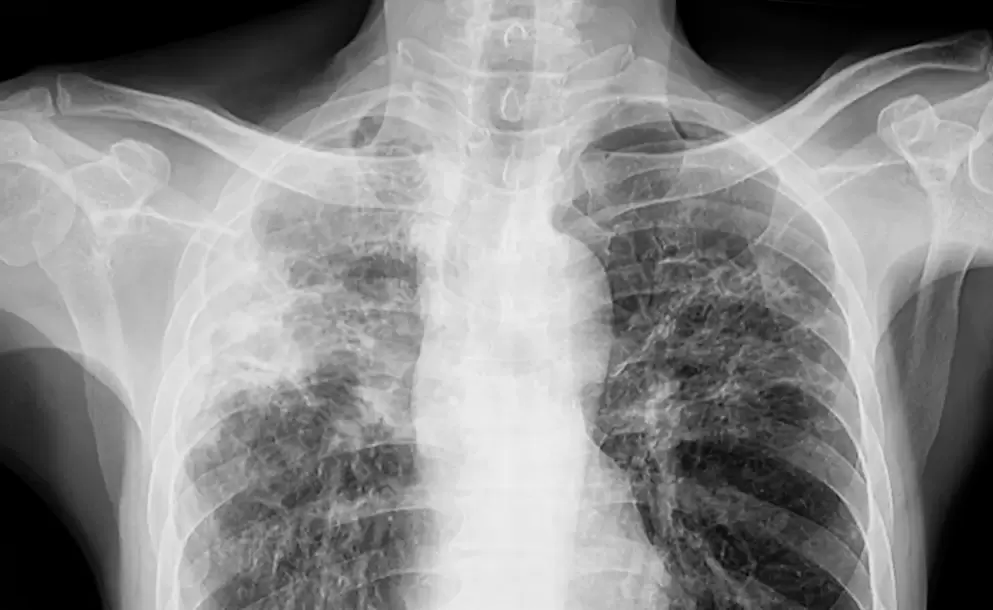

La tuberculosis es una enfermedad infecciosa causada por una bacteria que afecta principalmente a los pulmones y se transmite por el aire, al toser, estornudar o hablar.